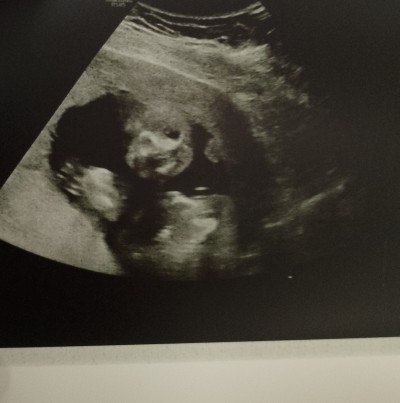

Cinsiyet tahmini yapabilen varmı

Gebelik haftası 9+5